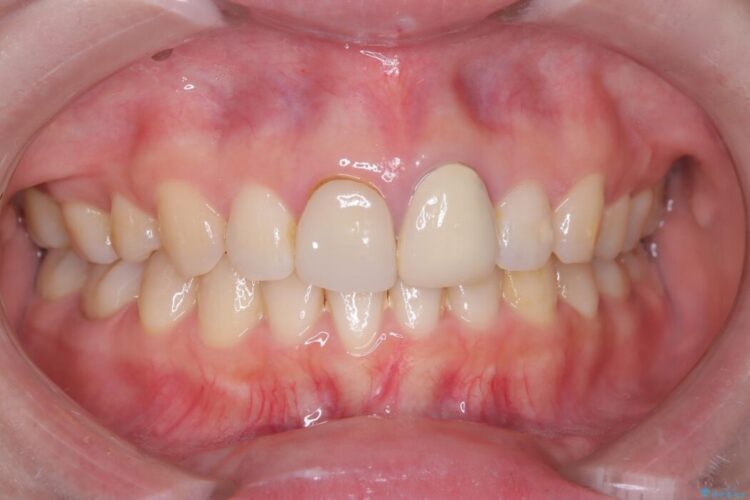

再根管治療とオールセラミックで前歯の気になる変色を解消

再根管治療とオールセラミックで前歯の気になる変色を解消 ビフォー 再根管治療とオールセラミックで前歯の気になる変色を解消 アフター

他院で神経を取った前歯が変色してきたとご相談にいらした患者様です。